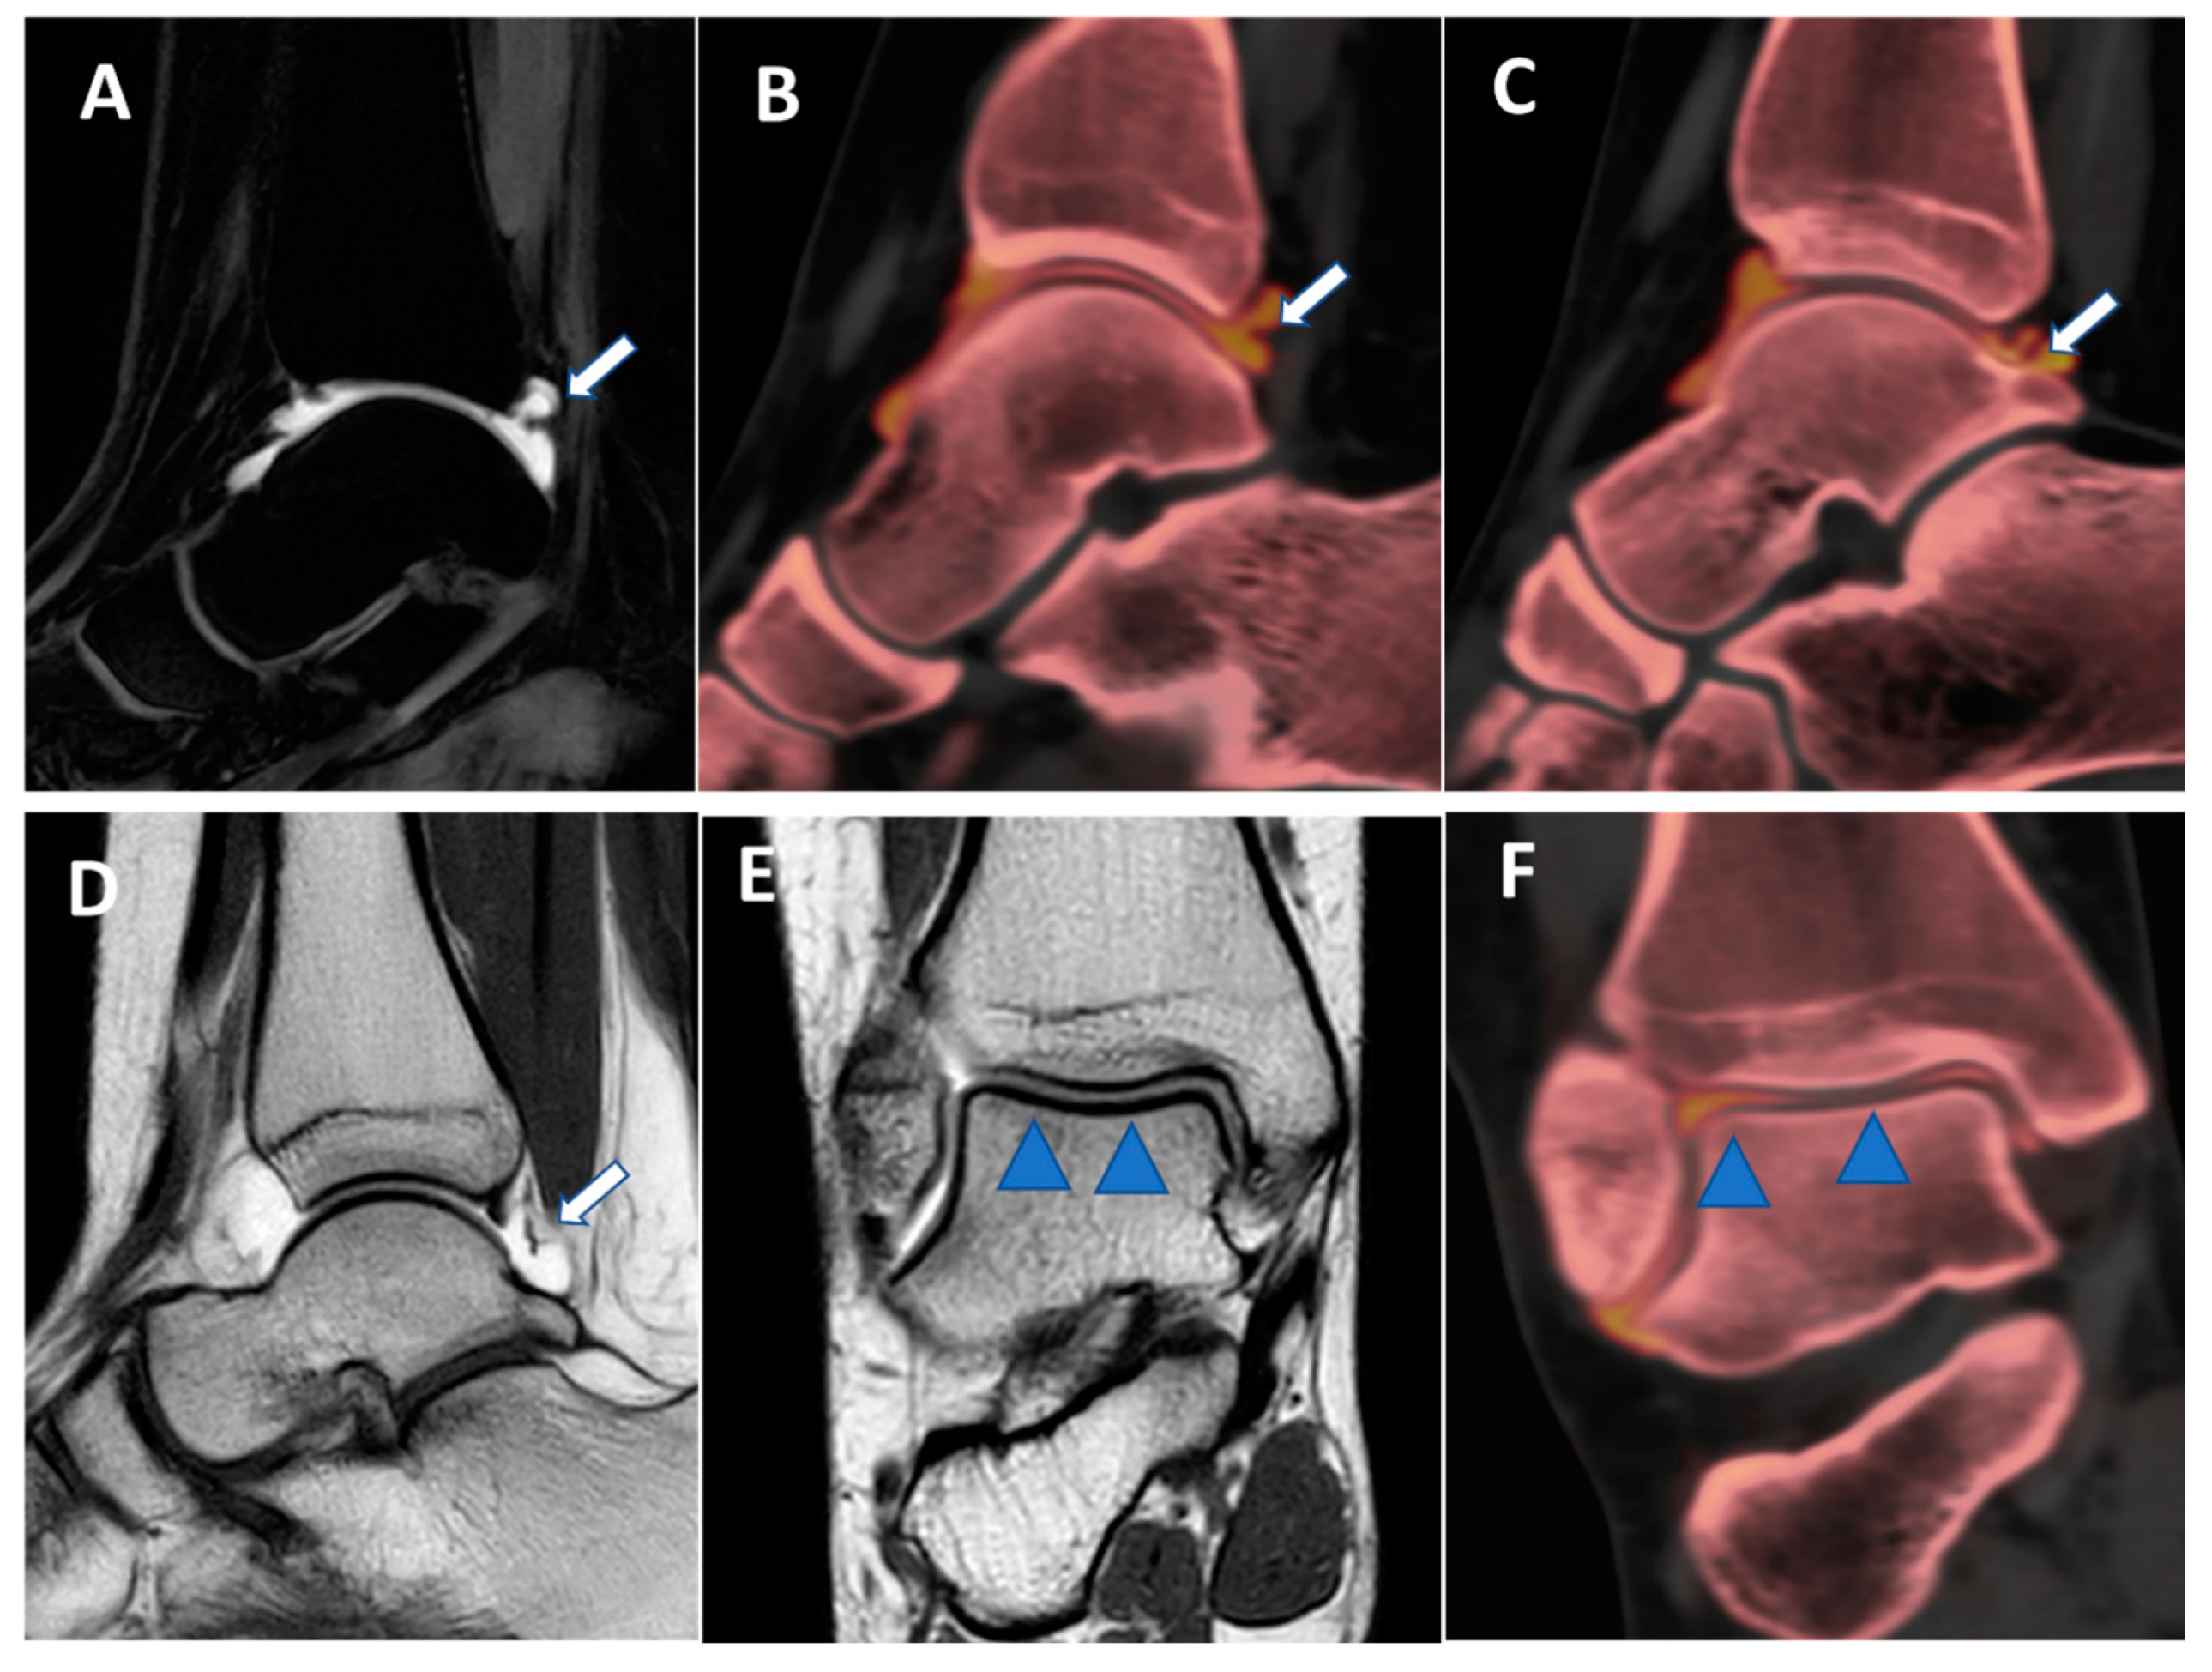

Figure 8.

Posterior capsular plica at ankle arthrograms. On 3 mm sagittal STIR and T1 weighted images (A,D), a thin posterior plica (arrow) is depicted. The same plica is nicely depicted on the corresponding sagittal 0.3 mm DECT iodine map images (arrows on (B,C)). On 3 mm Coronal T1 weighted images (E), a partial volume effect may hinder subtle cartilage defects (blue arrowheads). On the corresponding 0.3 mm coronal DECTA (F), articular cartilages are optimally imaged without any artifacts.

Figure 9.

Lateral plica syndrome at elbow arthrography. On the 3 mm coronal STIR and T1 weighted images (A,B), a tiny lateral plica (arrow) is depicted. The same plica is nicely depicted (arrow) on the corresponding reconstructed coronal 0.5 mm DECT iodine map image (C). On the 3 mm axial T1 weighted image (D), a partial volume effect does not allow for the correct image of the plica (arrow) and articular cartilages. On the corresponding 0.5 mm axial DECTA (E,F), the plica (arrow) and the adjacent articular cartilages are beautifully visualized without any artifact.